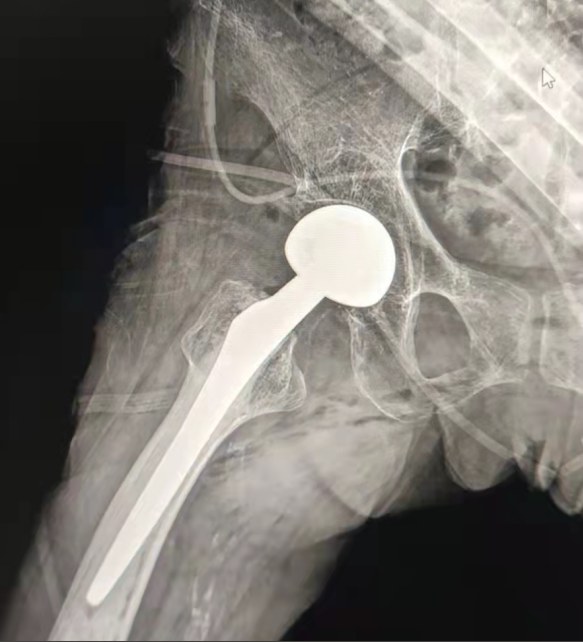

Case Sharing | A 70 years-old patient, received the total hip replacement with Lepu cemented hip system

Cemented Hip System:

Co-Cr-Mo Alloy Material

High wear resistance

Great mechanical strength

Shoulder Thread Design

Easily install,hold and adjust angle

Polished Surface Treatment

To achieve excellent bone ingrowthEnsuring the stability of early fixation

12/14 Standard taper design

Proximal Mix Anatomy

Design Collection Europe and USA Stem Features

Distal Both sides Adge Cutting Treatment

Reduce pressure in medullary cavity